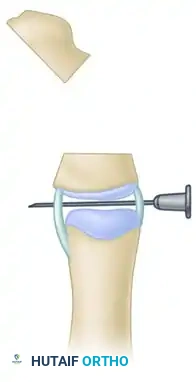

Step E: Completion of the Osteotomy

Using a fine oscillating saw or sharp osteotome, complete the transverse osteotomy through the delta phalanx, utilizing the needle as a guide to ensure the cut is perfectly parallel to the joint surface.

Step F: Closing Wedge Formation

The combined osteotomies (the initial physeal excision and the transverse cut) effectively form a closing wedge. Reduce the osteotomy by closing the wedge; this simultaneously shortens the abnormally long segment and realigns the longitudinal axis of the thumb.

Step G: Osseous Fixation

Secure the realigned bone ends with one or two smooth longitudinal Kirschner wires driven across the osteotomy site and the adjacent joint. These wires are typically left in place for 4 to 6 weeks until radiographic union is achieved.